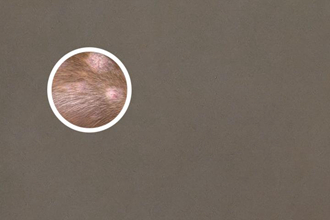

伍德氏燈是一種使用紫外線照射皮膚的設(shè)備,通過觀察皮膚在紫外線下的反應(yīng)來幫助醫(yī)生判斷疾病類型。在色素脫失斑的檢查中,伍德氏燈可以檢測(cè)出熒光現(xiàn)象,進(jìn)而確定斑塊的類型。不同類型的色素脫失斑在伍德氏燈下呈現(xiàn)出不同的熒光顏色和分布模式,這對(duì)于醫(yī)學(xué)醫(yī)生來說具有重要的診斷參考價(jià)值。

根據(jù)熒光特征,色素脫失斑通??梢苑譃閮深悾赫裏晒庑秃头礋晒庑?。正熒光型指的是斑塊在伍德氏燈下發(fā)出正規(guī)或黃正規(guī)熒光,這通常與表皮色素脫失有關(guān);反熒光型指的是斑塊在伍德氏燈下不發(fā)出熒光,這可能與深層色素脫失有關(guān)。通過觀察熒光特征,醫(yī)生可以初步判斷色素脫失斑的類型,并進(jìn)一步確定病因和治療方案。

通過伍德氏燈檢查,醫(yī)生可以觀察患者皮膚上的色素脫失斑是否會(huì)顯示出熒光。熒光的產(chǎn)生是由于白癜風(fēng)患者皮膚中存在的大量亮白色細(xì)胞或白斑,這些區(qū)域在特定的紫外線光照射下會(huì)發(fā)出正規(guī)或藍(lán)色的熒光。因此,如果患者的色素脫失斑在伍德氏燈下顯示出熒光,通常表示這是白癜風(fēng)的一種特征。

伍德氏燈下的熒光現(xiàn)象可以幫助醫(yī)生確定白癜風(fēng)的區(qū)域范圍和程度。通過觀察熒光的強(qiáng)度和形狀,醫(yī)生可以判斷病情的嚴(yán)重程度,并制定相應(yīng)的治療方案。熒光的顯示還有助于與其他皮膚病進(jìn)行區(qū)分,一些正確的診斷和治療。